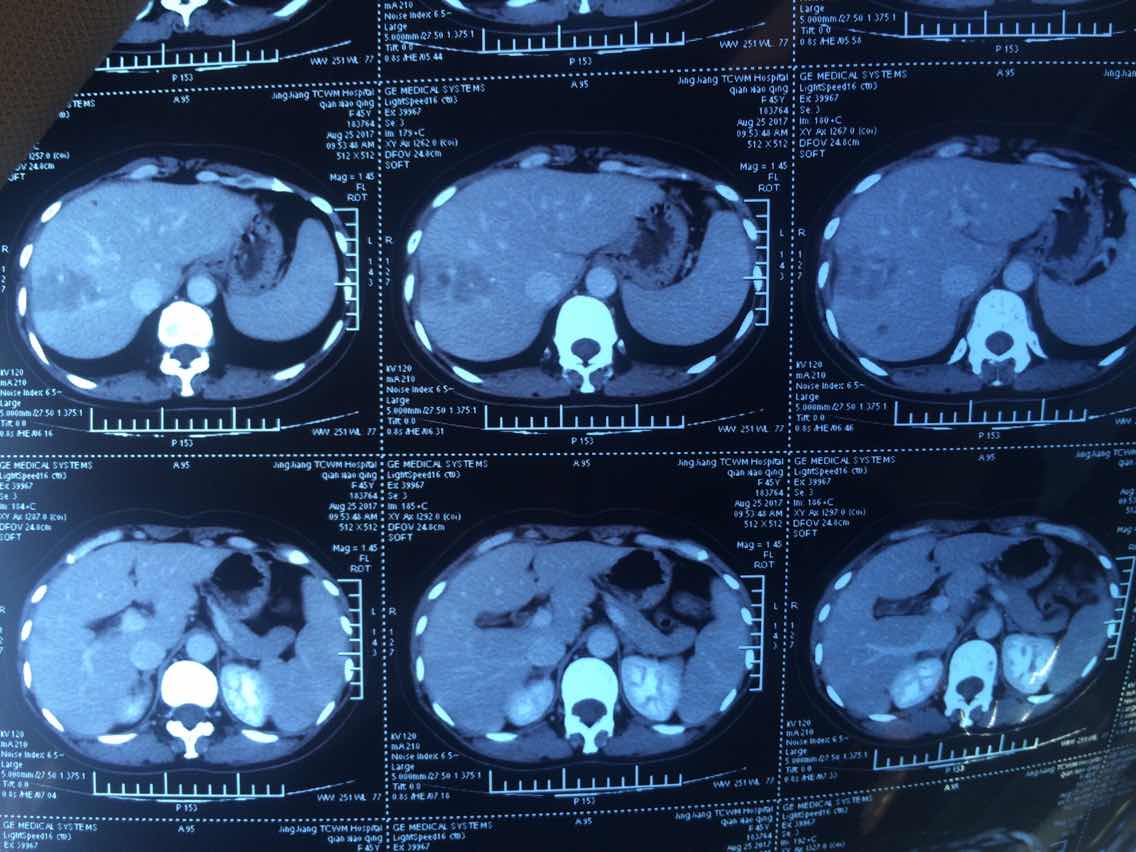

2017.10.29ct

举报

2017-11-01 01:40:02 有用(0)

回复(0)

2017.10.29

2017-10-31 10:44:24 有用(0)

2

2017-10-31 10:44:42 有用(0)

3

2017-10-31 10:45:01 有用(0)

4

2017-10-31 10:49:33 有用(0)

5